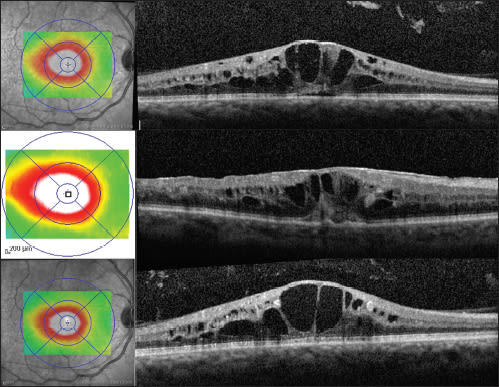

Case 4: Ischemic Considerations. A 70-year-old Asian male with a history of diabetes mellitus, kidney transplant (on immunosuppressive therapy) and thrombocytopenia was referred to the retina service due to loss of vision and CRVO in his left eye two months after cataract surgery. Prior to referral, his VA was 20/25, and after presentation, it was counting fingers at two feet in the left eye. Also on examination, his IOP was 29 mm Hg, and he had neovascularization of the iris and in three quadrants of his angle on gonioscopic examination. The dilated fundus examination was consistent with CRVO with macular edema, and SD-OCT confirmed this (Figure 6, top).

Figure 6. Case 4: A 70-year-old Asian male with ischemic CRVO in the right eye. Large amount of CME and subretinal fluid is present (top). After two intravitreal Lucentis injections, retinal thickness decreased (middle). At most recent follow up after monthly injections, SD-OCT shows less CME (bottom) although the VA remained counting fingers the whole while.

He underwent panretinal laser photocoagulation and an intravitreal injection of ranibizumab in the left eye on the same day. Over the next two months, he received additional fill-in PRP and two more ranibizumab injections, with no change in his vision, although improvement in the retinal thickness on SD-OCT (Figure 6, middle). All iris and angle neovascularization regressed, and intraocular pressure normalized.

He received additional monthly ranibizumab injections, and on most recent follow-up, his visual acuity was still counting fingers, intraocular pressures were normal, and SD-OCT demonstrated considerable improvement in retinal thickness (Figure 6, bottom).

This is an uncommon, though typical enough, scenario for an ischemic RVO sequela. Nonperfused CRVO is suggested by vision that is worse than 20/200, a relative afferent pupil defect, and the presence of cotton-wool spots and large, confluent hemorrhages.12 Fluorescein angiography is commonly performed to assess the severity of macular edema and the perfusion status. OCT was used to quantify macular edema and assess treatment response.

The point of this case is that OCT played no role whatsoever in the decisional process in terms of treatment for the ischemic peripheral retina, nor did the improvement in any way correlate with the VA change. It did, however, act as a marker for demonstrating anatomic improvement and visible proof—for the physician, patient and his family—that the retinal appearance was improving with continued treatment.